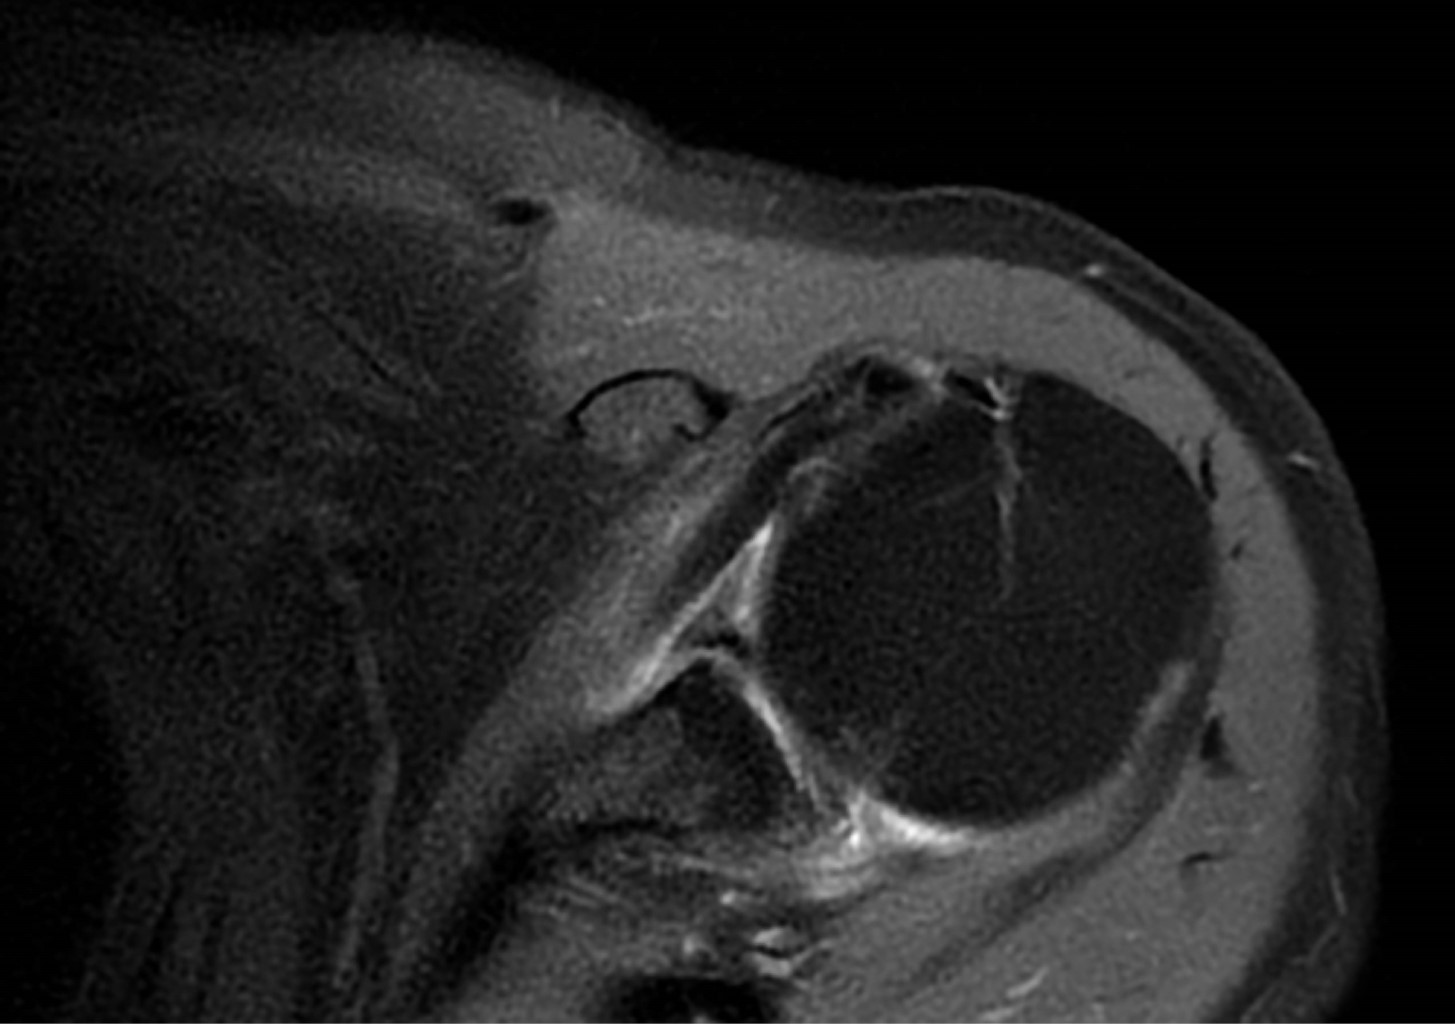

Duplicity of the long portion of the biceps, an anatomical variant poorly described

Articular pain is one of the most common reasons for a medical consultation because shoulder pain is frequent. Anatomical variants may cause confusion during diagnosis among radiologists and surgical treatment for trauma doctors. We will talk about a patient who comes for a magnetic resonance without contrast of the shoulder, for which we found many pathologies, such as the duplicity of the long head of the biceps.

Figure 2